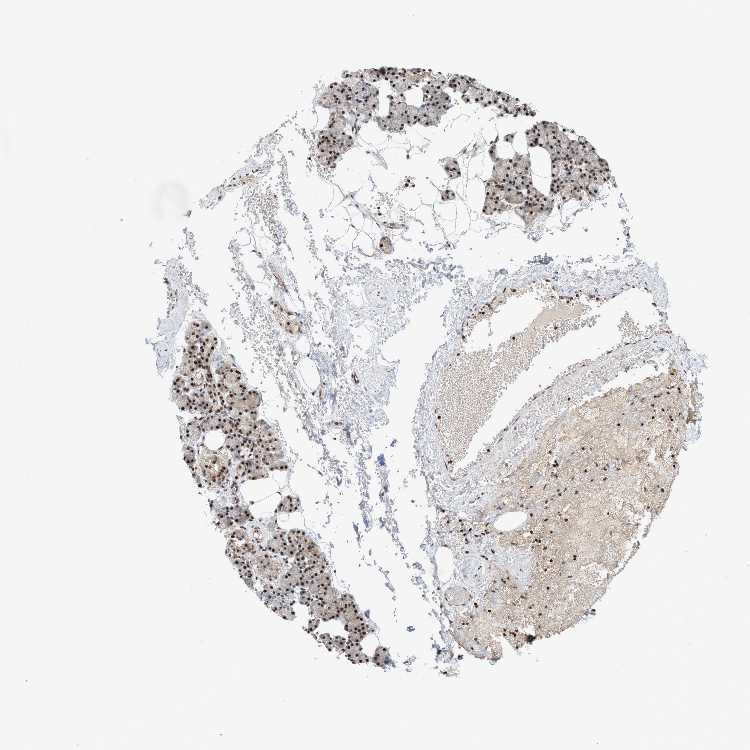

SALIVARY GLAND - Antibody stainingi

Antibody staining in the annotated cell types in the current human tissue is reported as not detected, low, medium, or high, based on conventional immunohistochemistry profiling in selected tissues. This score is based on the combination of the staining intensity and fraction of stained cells.

Each image is clickable and will lead to virtual microscopy that enables deeper exploration of all samples and also displays staining intensity scores, fraction scores and subcellular localization as well as patient and tissue information for each sample.

Antibody HPA021557Antibody HPA024646

Glandular cells HighHigh